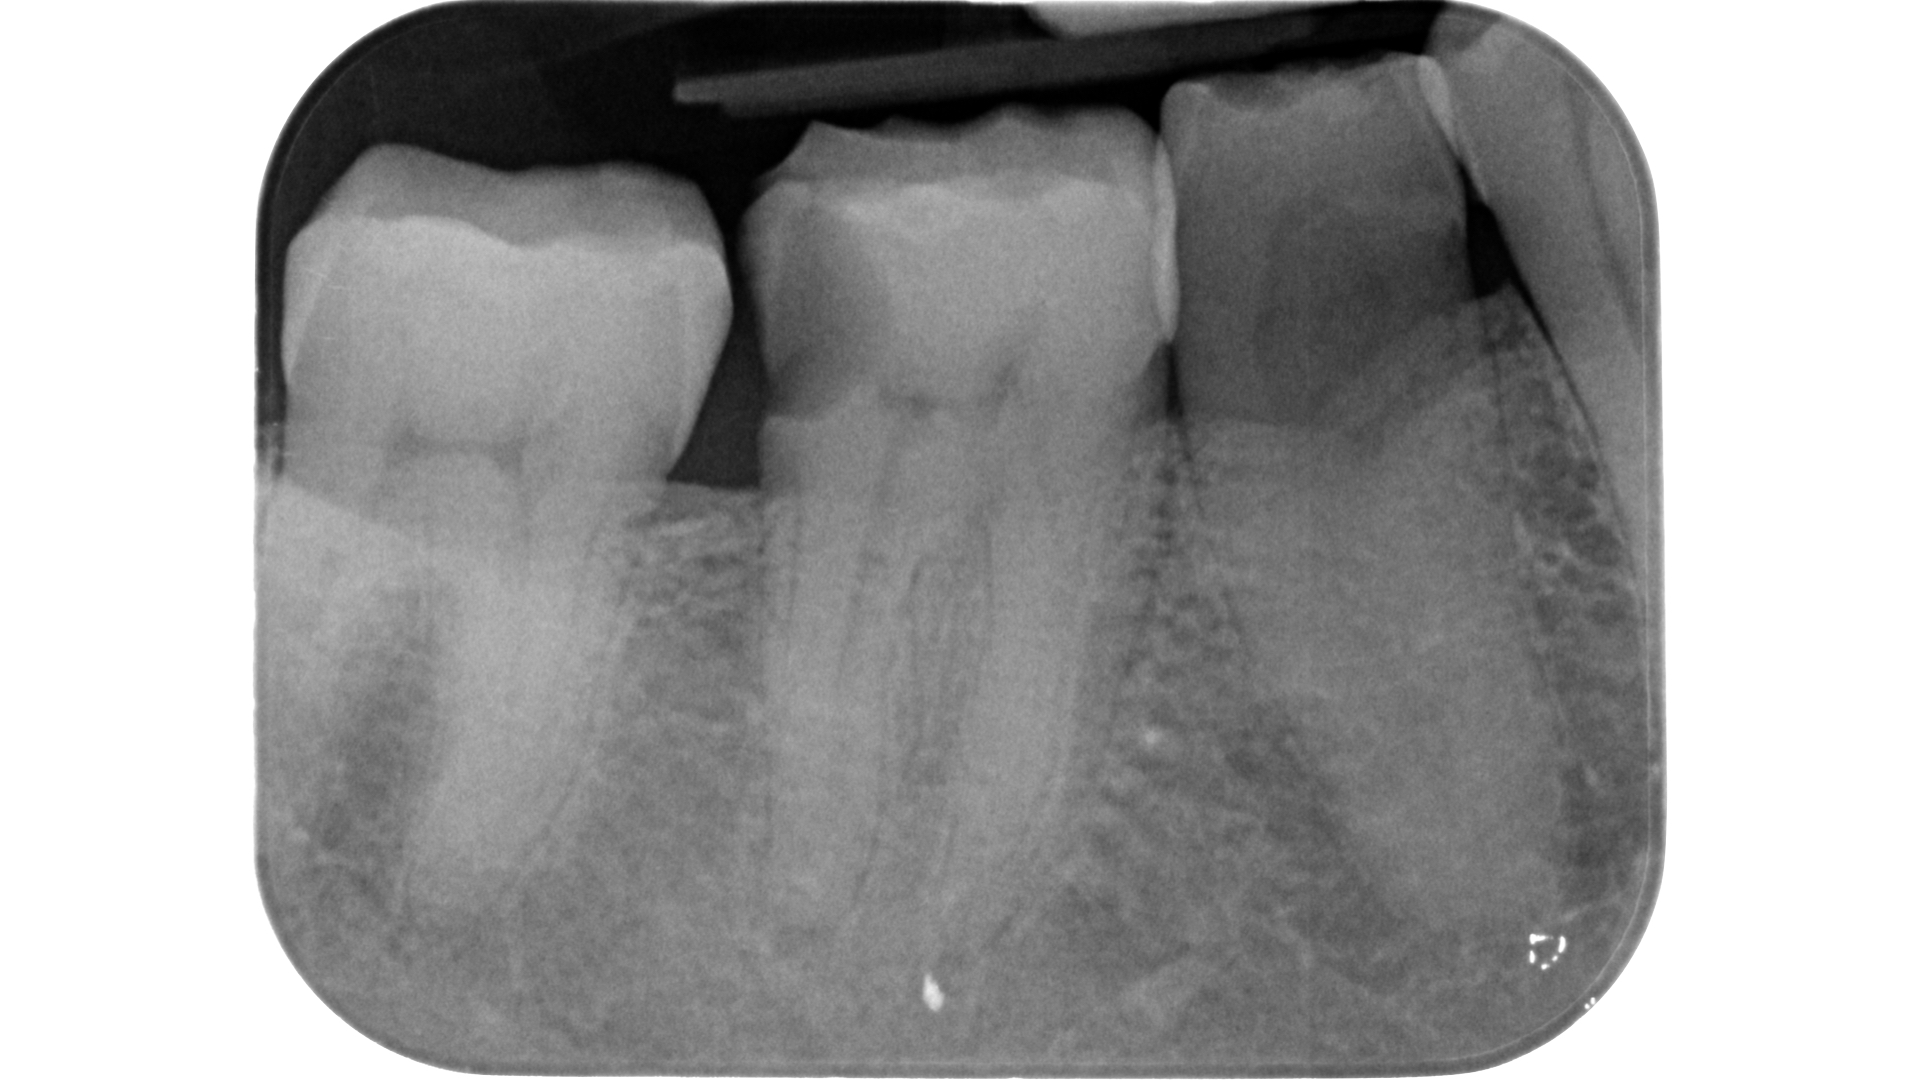

Devono essere valutate con molta attenzione la posizione dell’elemento in arcata e la sua inclinazione (Figure 6-7), l’entità e la posizione del processo carioso se presente, gli eventuali restauri posizionati sul dente e i rapporti con il parodonto: tutte queste considerazioni permetteranno al clinico di capire innanzitutto la mantenibilità e la possibilità di isolare mediante diga di gomma il dente. L’interpretazione degli esami radiografici consentirà inoltre di valutare alcuni parametri preoperatori di notevole importanza:

- presenza di radiotrasparenze periradicolari o periapicali;

- aspetto della camera pulpare e del sistema canalare;

- anatomia radicolare e canalare;

- presenza di pregresse terapie canalari e valutazione della qualità delle stesse;